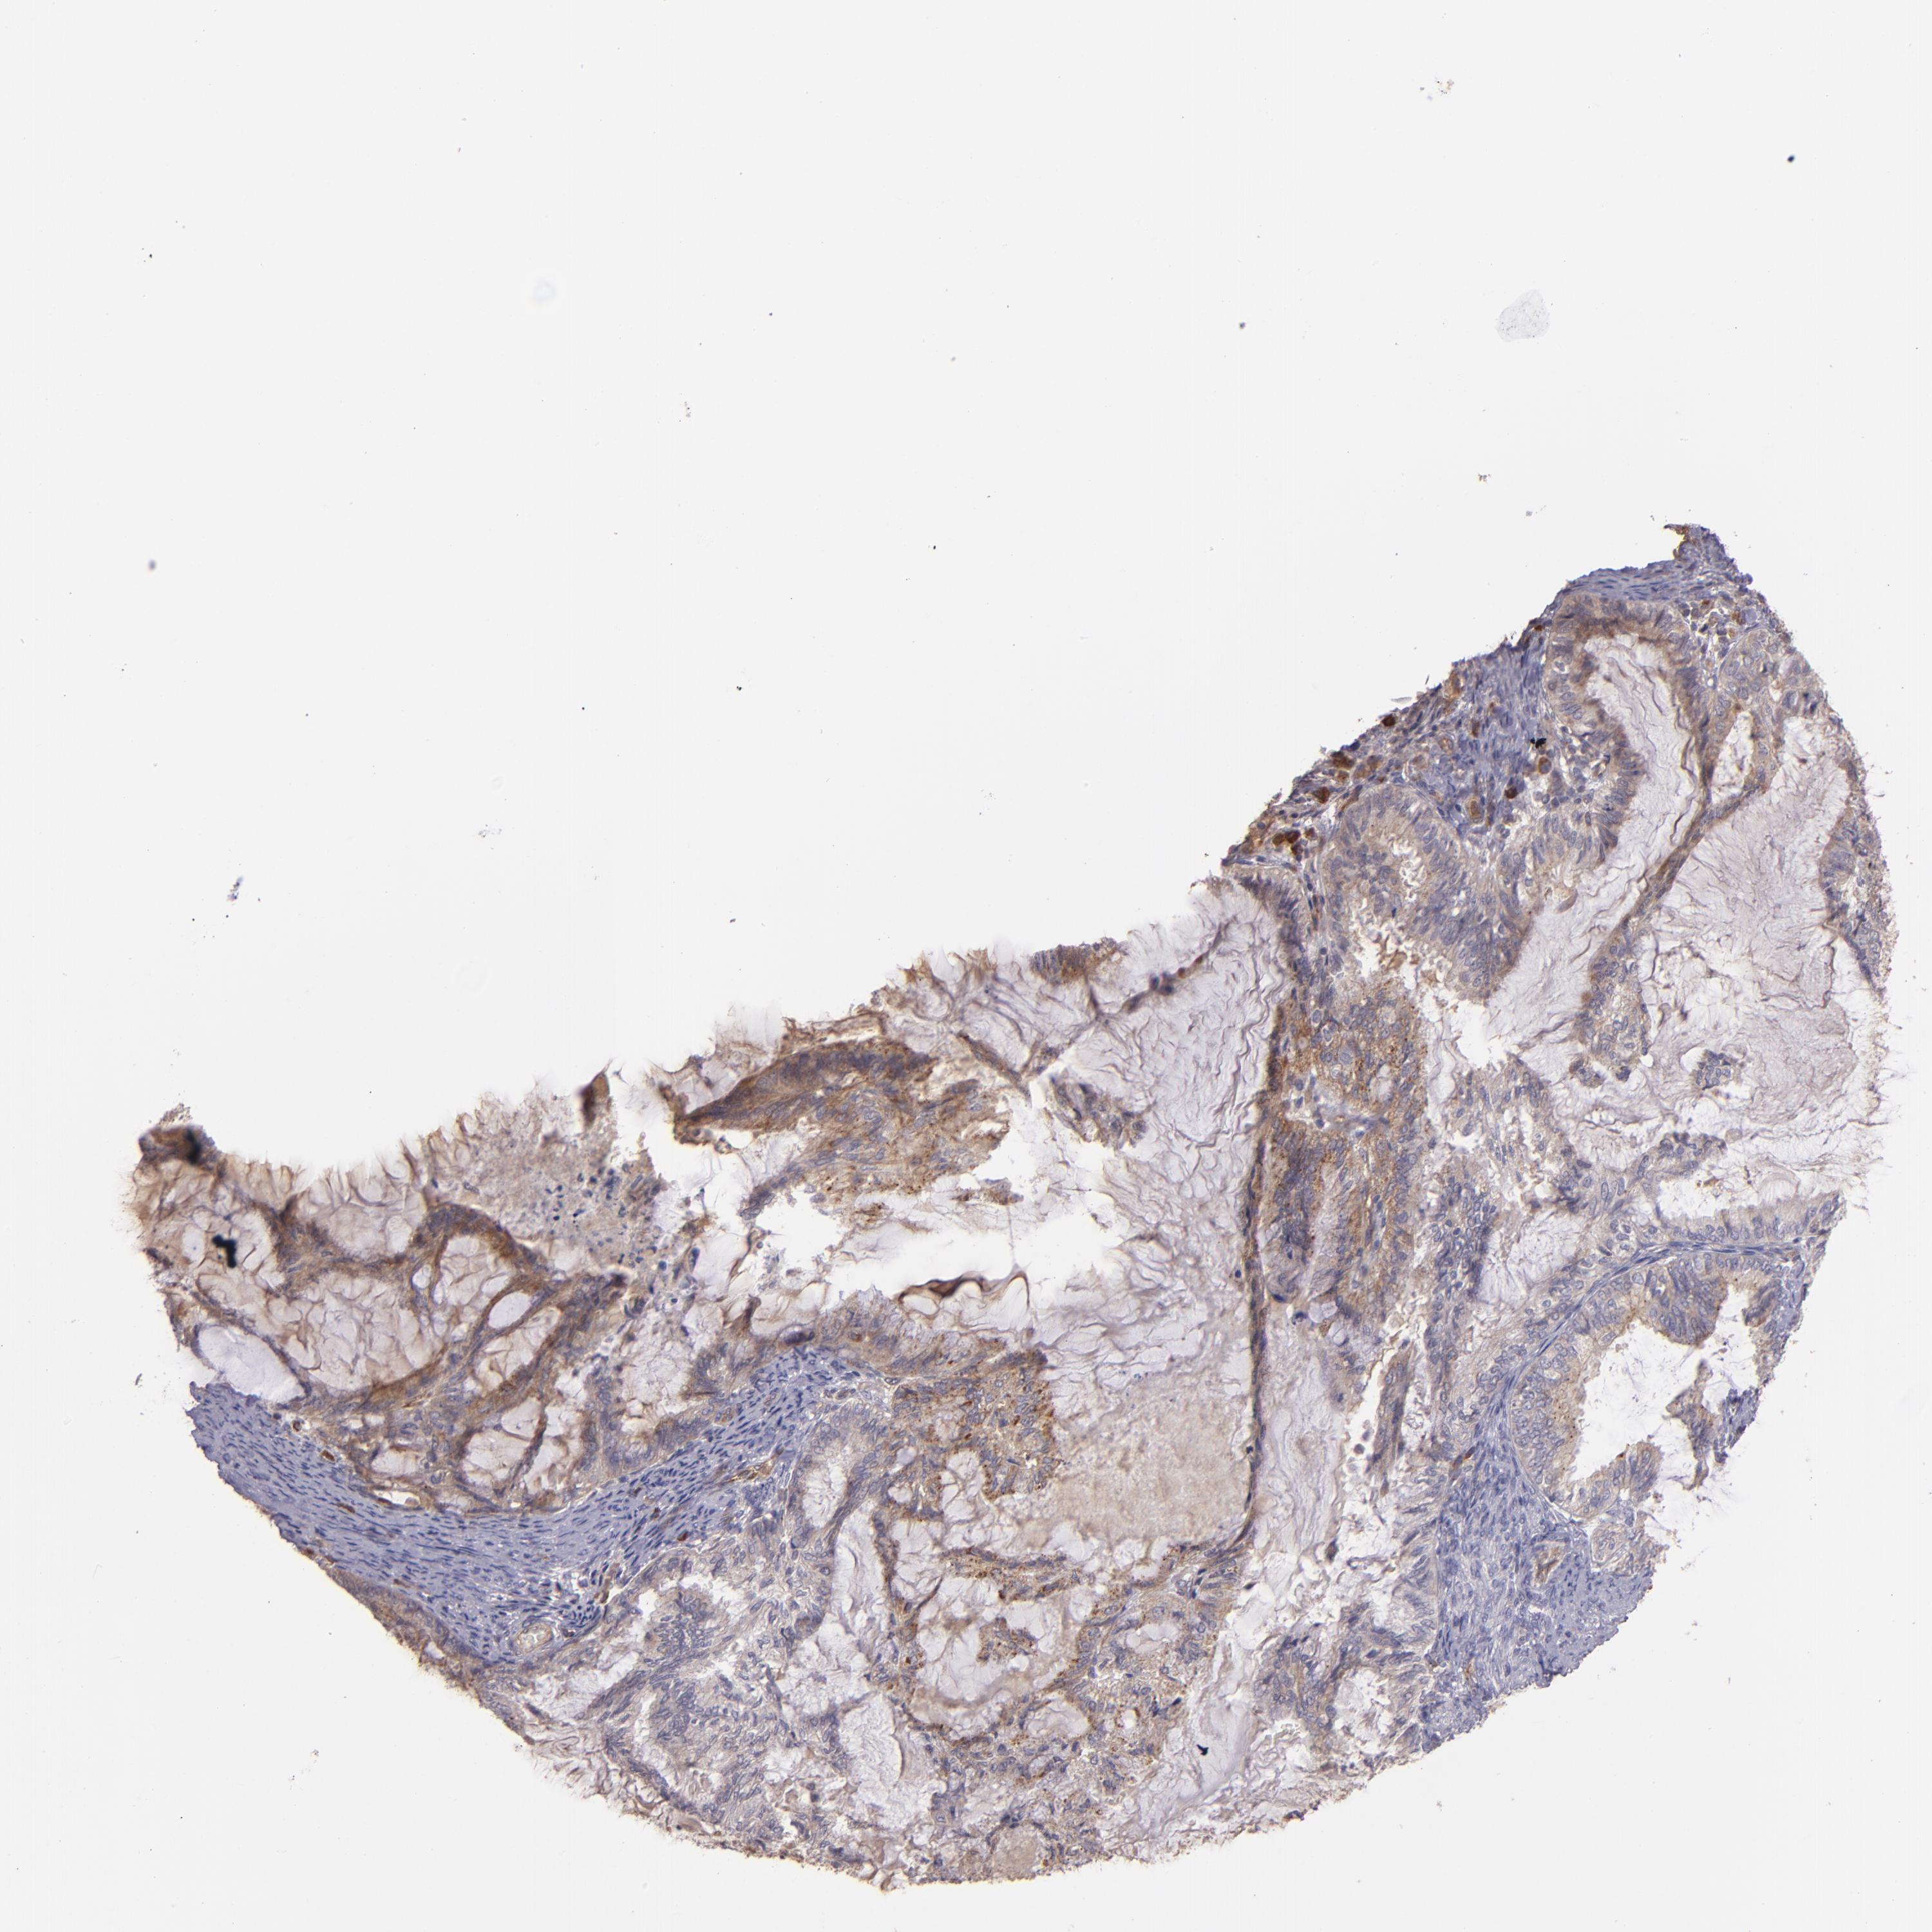

ENDOMETRIAL CANCER - Protein expressioni

A mouse-over function shows sample information and annotation data. Click on an image to view it in a full screen mode. Samples can be filtered based on level of antibody staining by selecting one or several of the following categories: high, medium, low and not detected. The assay and annotation is described here.

Note that samples used for immunohistochemistry by the Human Protein Atlas do not correspond to samples in the TCGA dataset.

Antibody stainingi

Antibody staining in the annotated cell types in the current human tissue is reported as not detected, low, medium, or high, based on conventional immunohistochemistry profiling in selected tissues. This score is based on the combination of the staining intensity and fraction of stained cells.

Each image is clickable and will lead to virtual microscopy that enables deeper exploration of all samples and also displays staining intensity scores, fraction scores and subcellular localization as well as patient and tissue information for each sample.

Antibody HPA001490

Antibody HPA013616

Staining

High

Medium

Low

Not detected

Intensity

Strong

Moderate

Weak

Negative

Quantity

>75%

75%-25%

<25%

None

Location

Nuclear

Cytoplasmic/membranous

Cytoplasmic/membranous,nuclear

Adenocarcinoma, NOS

Neoplasm, malignant, NOS